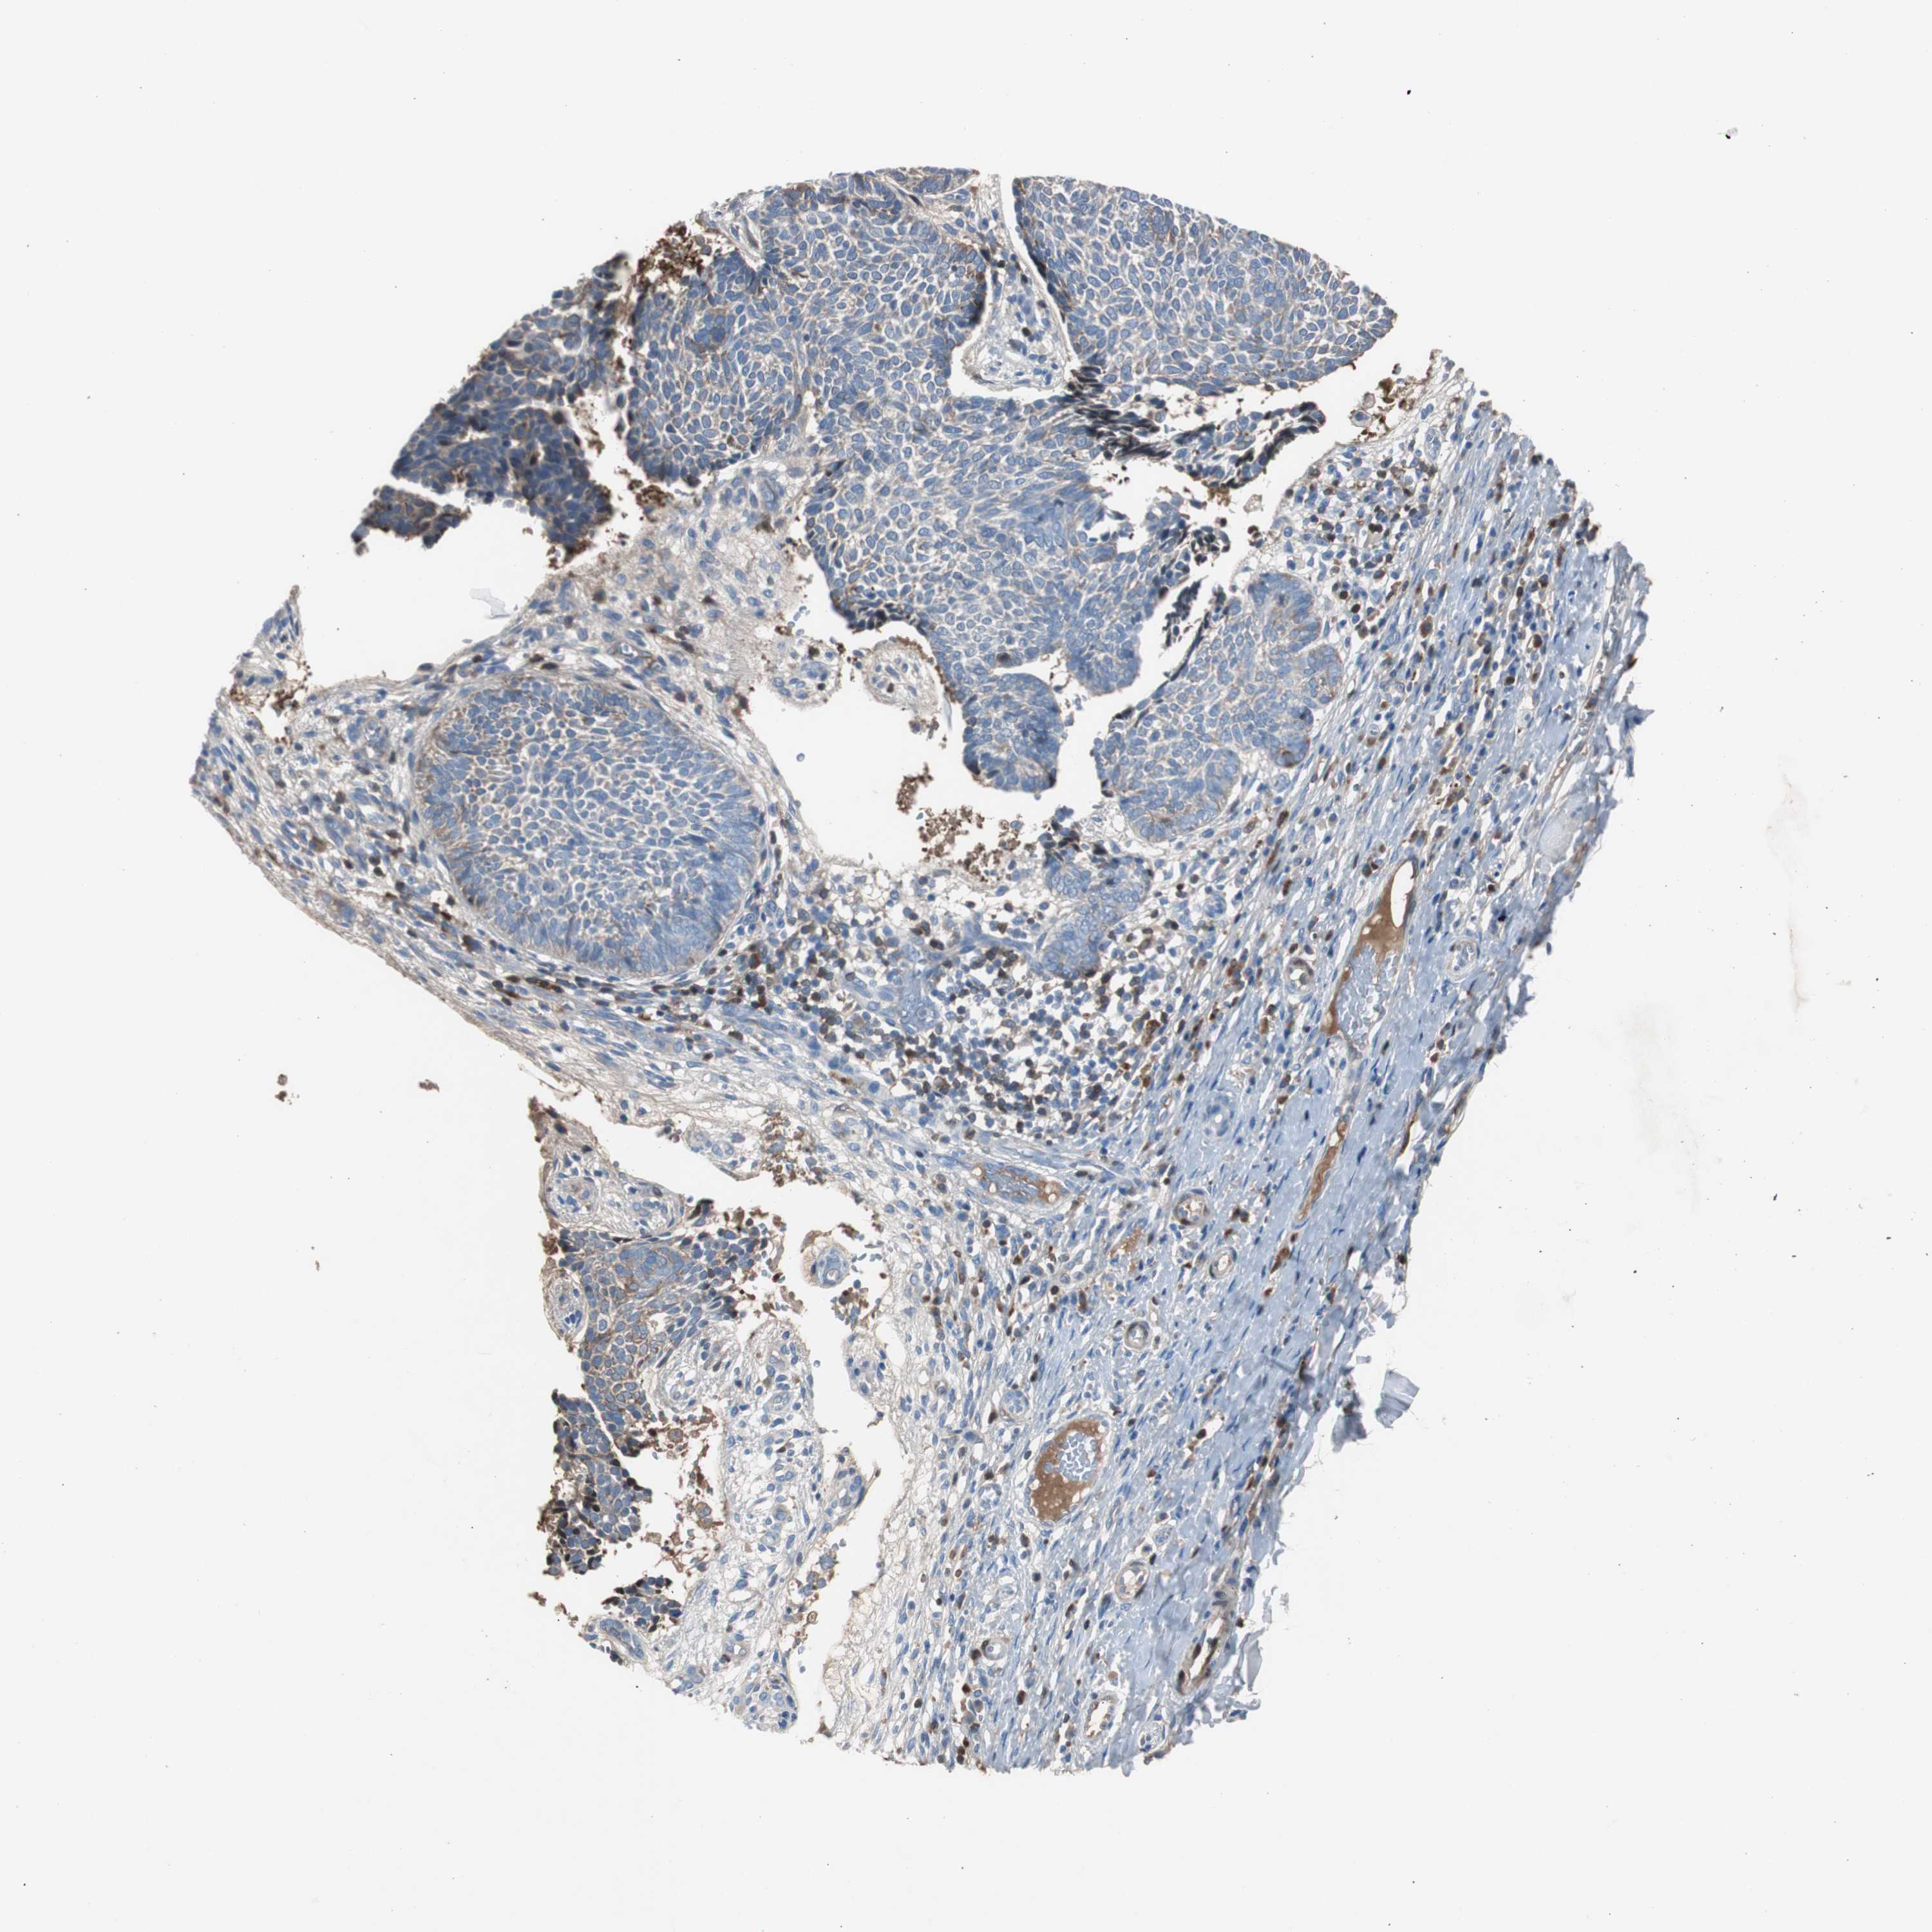

SKIN CANCER - Protein expressioni

A mouse-over function shows sample information and annotation data. Click on an image to view it in a full screen mode. Samples can be filtered based on level of antibody staining by selecting one or several of the following categories: high, medium, low and not detected. The assay and annotation is described here.

Antibody stainingi

Antibody staining in the annotated cell types in the current human tissue is reported as not detected, low, medium, or high, based on conventional immunohistochemistry profiling in selected tissues. This score is based on the combination of the staining intensity and fraction of stained cells.

Each image is clickable and will lead to virtual microscopy that enables deeper exploration of all samples and also displays staining intensity scores, fraction scores and subcellular localization as well as patient and tissue information for each sample.

Antibody HPA005825

Squamous cell carcinoma, NOS

Basal cell carcinoma